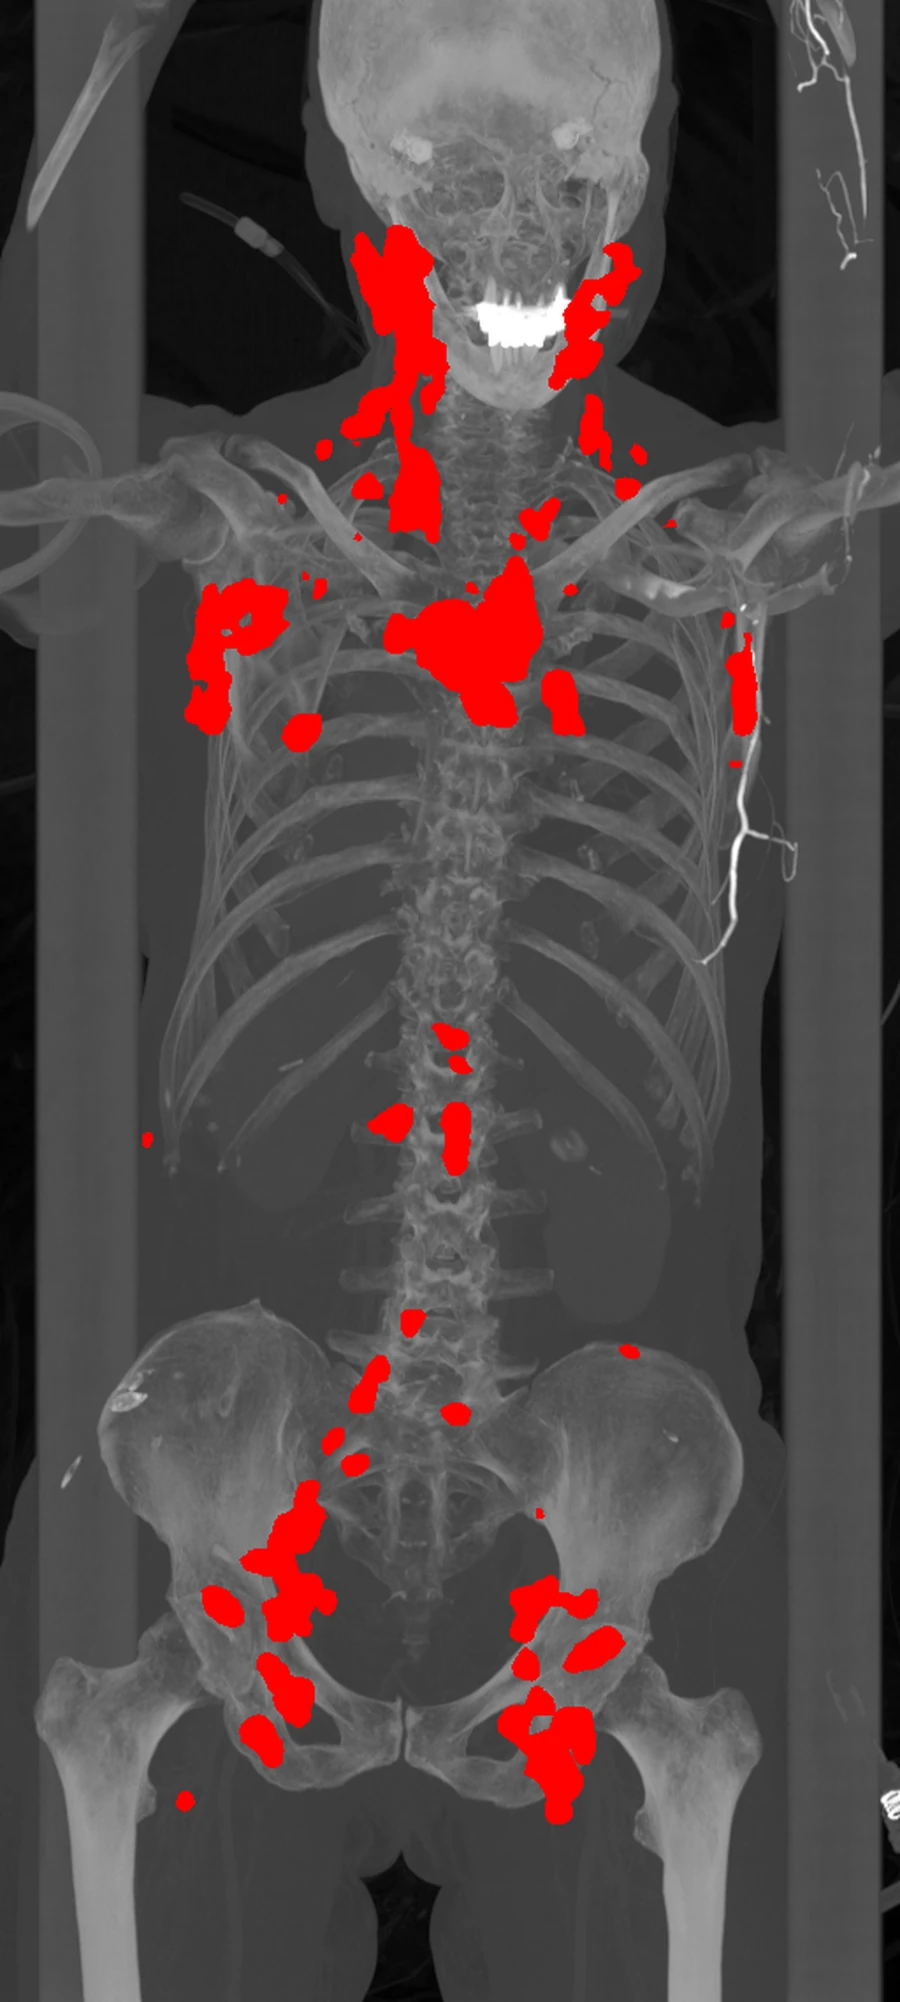

Whole-body segmentation mask from a DLBCL PET/CT case

Key output A tumor mask that can be measured The highlighted regions are the software’s segmentation output. Once the disease is outlined accurately, the pipeline can calculate tumor volume, lesion burden, radiomics features, and downstream modeling variables from the same case.

Tumor outline Burden metrics Radiomics export